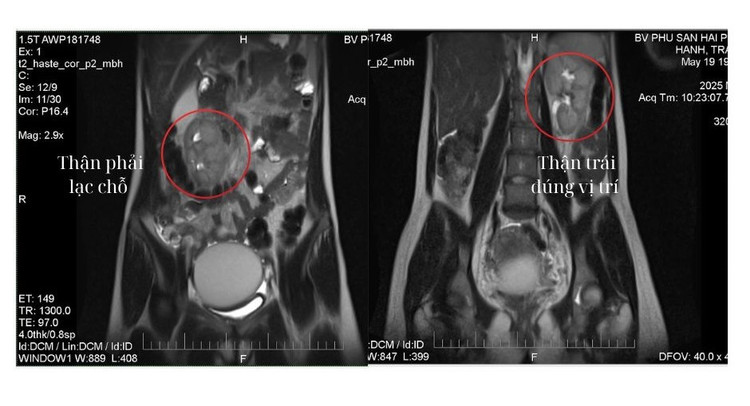

Qua thăm khám lâm sàng kết hợp siêu âm và chụp cộng hưởng từ (MRI), phát hiện khối u lạc nội mạc buồng trứng trái kích thước lớn (d=66 x 75 x 86 mm).

Khối u lạc nội mạc buồng trứng trên nền thận lạc chỗ - Ảnh BVCC

Tuy nhiên, ca bệnh lại đặc biệt phức tạp do bệnh nhân đồng thời mắc dị tật bẩm sinh – thận phải lạc chỗ (thận phải nằm ở thành bụng trước bên phải) làm tăng nguy cơ tổn thương thận và niệu quản trong quá trình phẫu thuật.